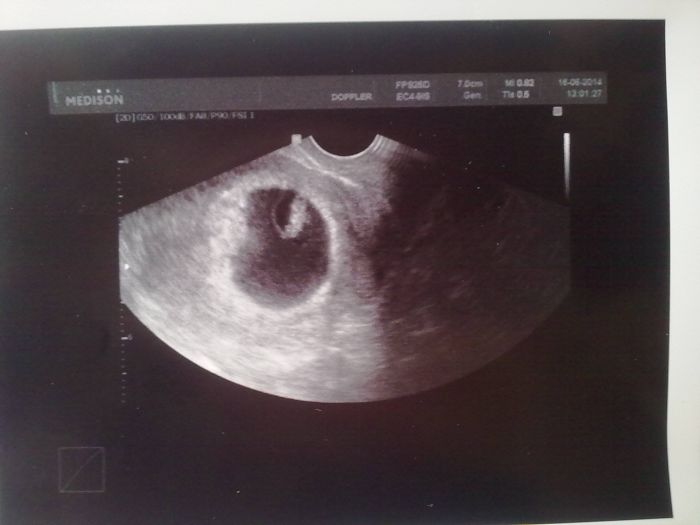

Ahoj holky. Tak jsme byli dneska na ultrazvuku, máme 7tt+4 podle velikosti, prcek má 12 mm

vše je v pořádku, srdíčko tluče. Přikládám i první fotečku. Průkazku dostanu až za 14 dní.

[567641]Fotečka krásná Evi,jen malý dodatek,mimčo má v této době už 1,2cm,12mm je málo

Bozanko, vždyť 12 mm je 1,2 cm :-D děkujeme, je to malý zázrak